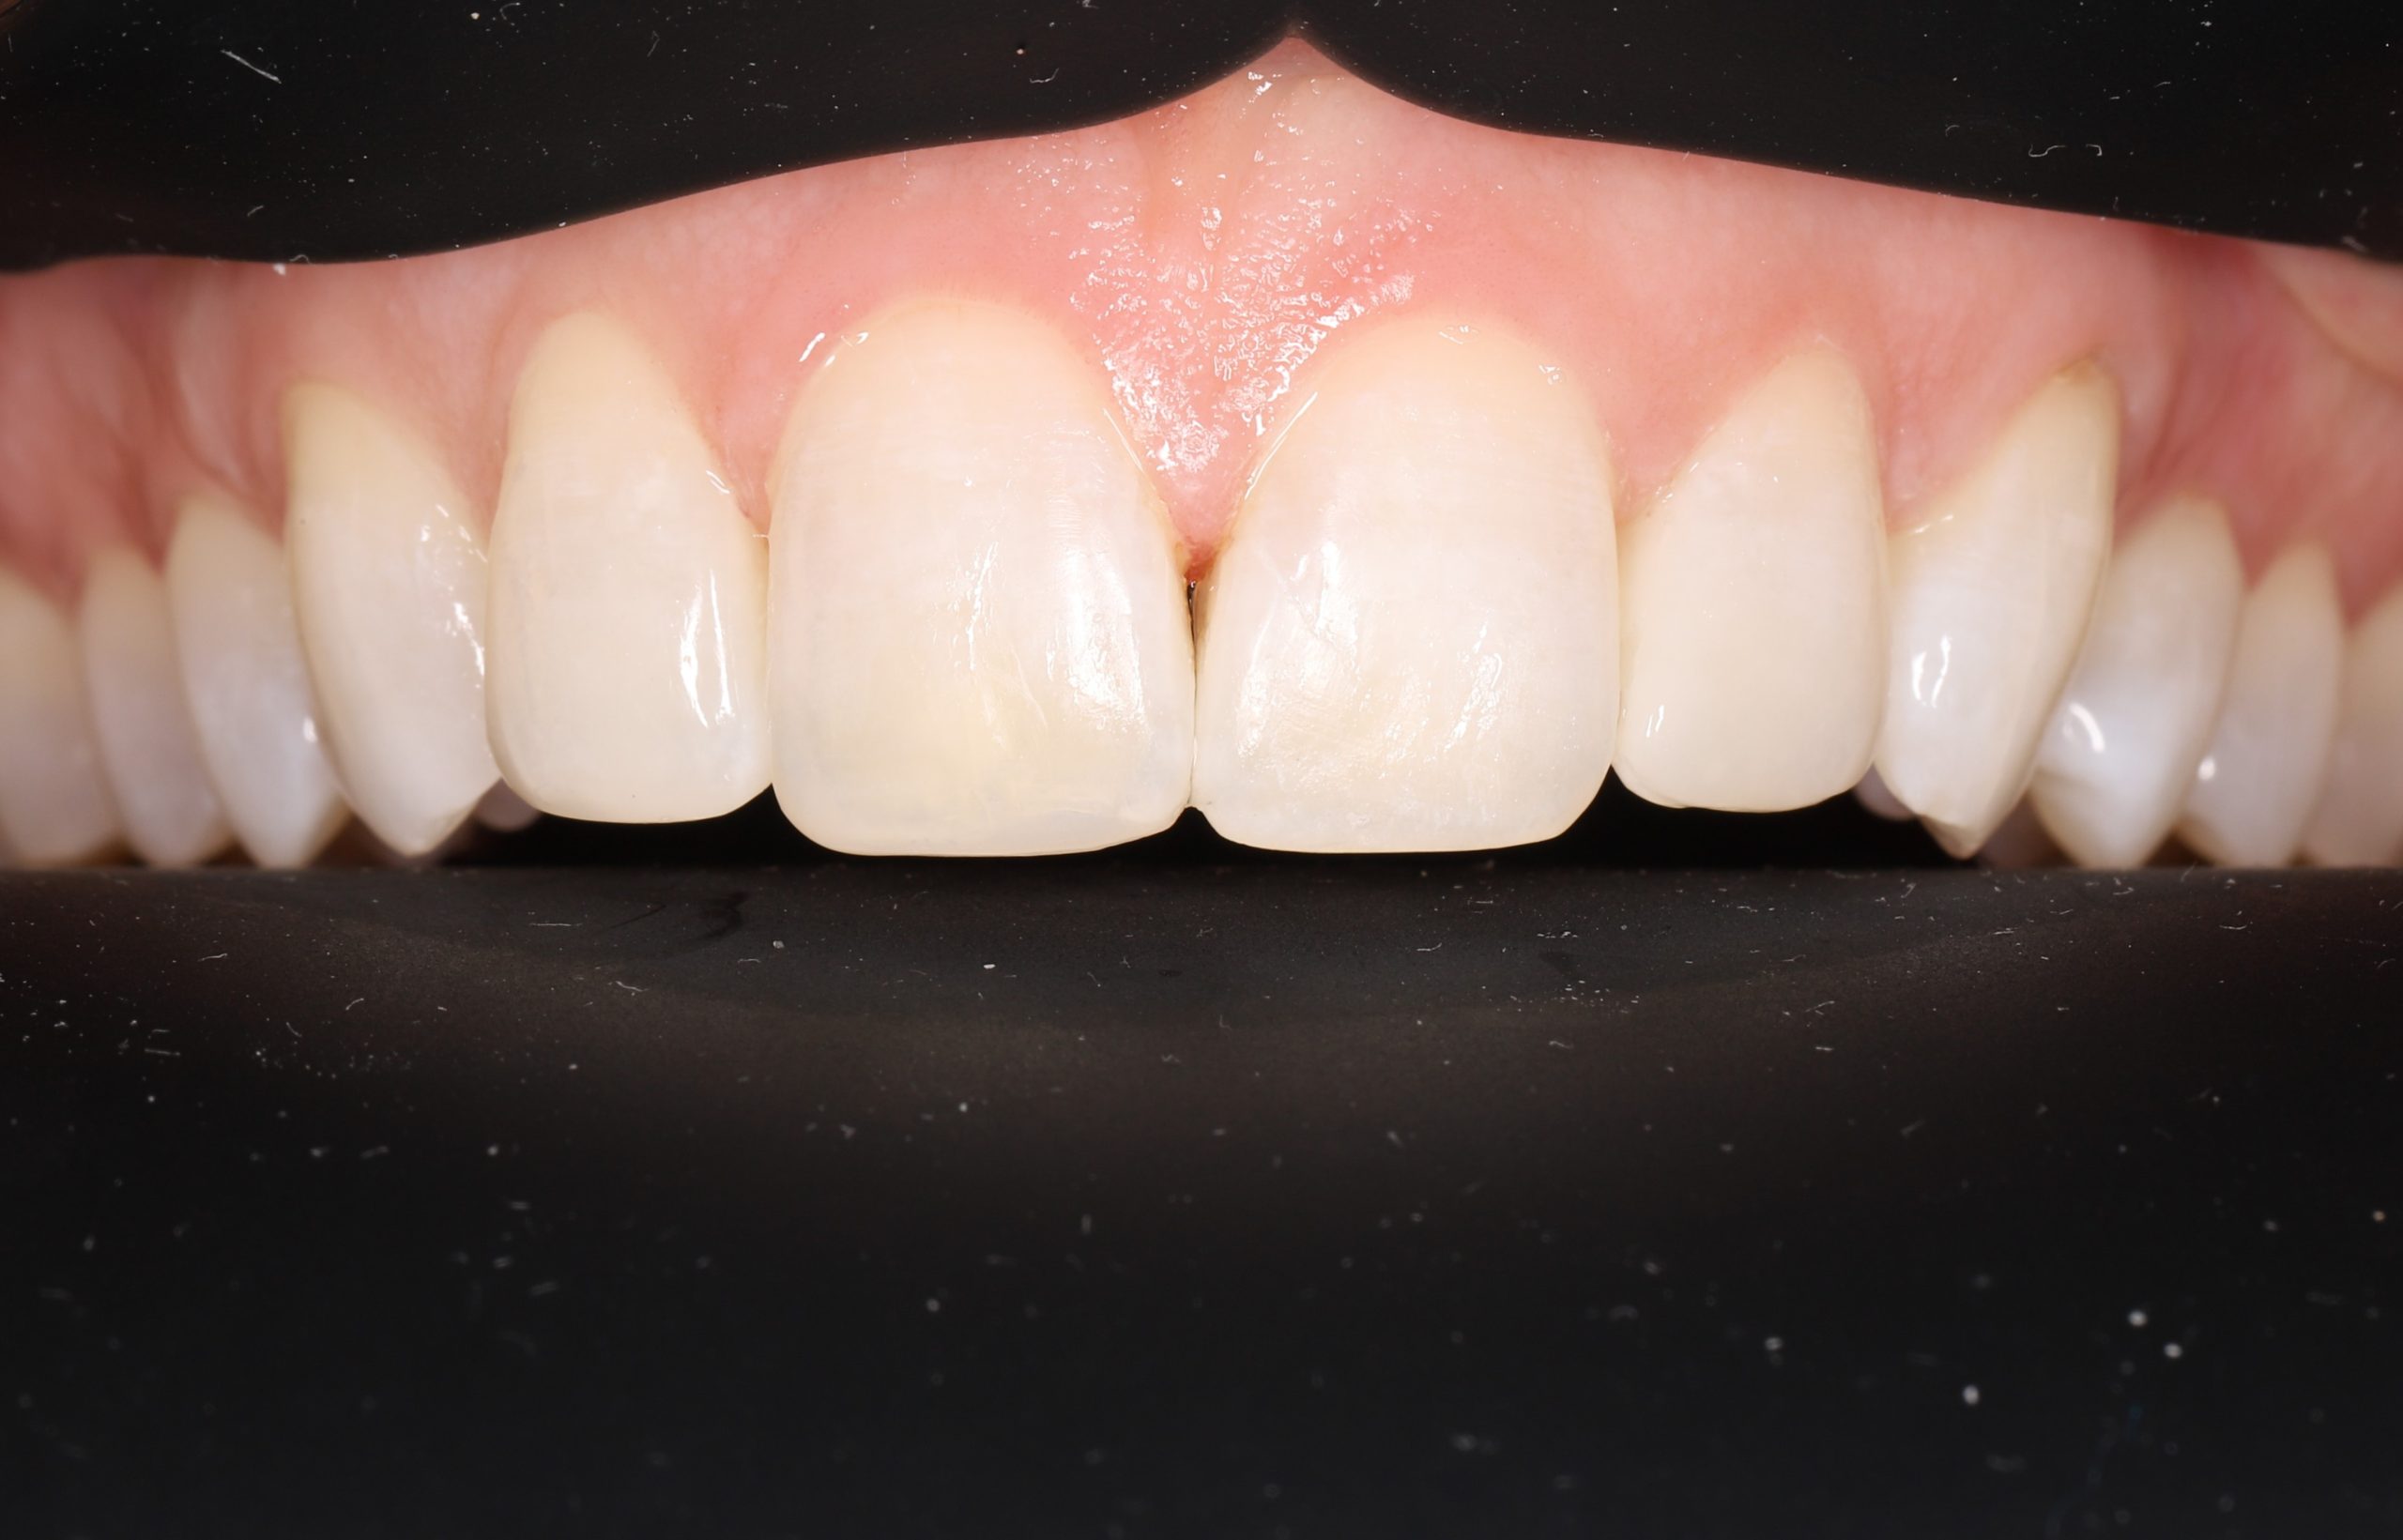

5. Final Polishing and Bite Adjustment

We contour and polish the surface to a high gloss and ensure your bite feels natural in all positions.

Aesthetic and Natural-Looking

The material matches your enamel, blending into the smile with virtually invisible transitions.

Minimally Invasive

Bonding preserves healthy enamel because it adheres to the tooth instead of requiring extensive reshaping.